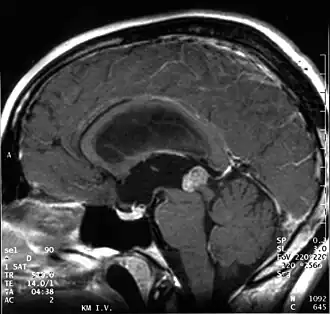

Kernspintomographie. Papillärer Tumor der Pinealisregion bei einem 18-jährigen Patienten (sagittale T1 gewichtete Aufnahme nach Kontrastmittel)

Aufgrund ihrer typischen Lage behindern papilläre Tumoren der Pinealisregion häufig den Fluss der Cerebrospinalflüssigkeit, was zu einer Erhöhung des Hirndrucks führen kann. Kopfschmerz, Übelkeit und Erbrechen sind unspezifische Symptome. Durch Druck des Tumors auf die Vierhügelplatte treten nicht selten Störungen der Okulomotorik mit Doppelbildern auf (Parinaud-Syndrom). In der Kernspintomographie stellen sich papilläre Tumoren der Pinealisregion als kontrastmittelanreichernde Raumforderungen dar.